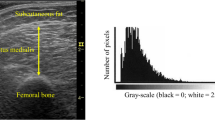

Individual thigh muscle CSAs were measured with manual segmentation using Medical Image Processing, Analysis, and Visualization software (MIPAV, v 7.1.1; National Institutes of Health, Bethesda, MD, USA) (Fig. 2). To calculate thigh muscle CSAs, those for rectus femoris (RF), VL, vastus intermedius (VI), VM, biceps femoris short head (BFS), biceps femoris long head (BFL), semitendinosus (ST), semimembranosus (SM), adductor (ADD), sartorius (SAR), and gracilis (GRA) were summed. To calculate knee extensor muscle, CSA, RF, VL, VI, and VM CSAs were summed. To calculate knee flexor muscle, CSA, BFS, BFL, ST, and SM CSAs were summed. The ratios of CSAs of the knee extensor, knee flexor, and ADD muscles to those of the thigh were calculated. The ratios of the individual knee extensor CSAs to the knee extensor and individual knee flexor CSAs to the knee flexor were calculated. The reproducibility of individual thigh muscle CSA measurement was excellent, as reported previously [18]. For the intraobserver reproducibility of the CSA measurement, the standard error of measurement (SEM) for the individual thigh muscle CSAs measurement was mean 3.7% and the SEM for the measurement of the individual thigh muscle CSA to muscle group ratios was mean 0.79%.

The dotted line represents the myofascial cross-sectional area (CSA) and solid lines are individual thigh muscle CSAs (left image). The white area within the myofascia is inter-MAT (muscle adipose tissue) (right upper quadrant), and the white area within individual muscle is intra-MAT (right lower quadrant)

Measurements of SAT, thigh inter-MAT, and individual thigh intra-MAT CSAs

Thigh circumference and myofascial CSA at the 10% distal region were semi-automatically segmented using MIPAV software (Fig. 1). Yoshiko et al. [19] reported that significant differences in the intra-MAT composition between healthy young individuals and elderly individuals were observed at the distal region of the thigh. Therefore, CSA at the 10% distal region was analyzed in the present study. SAT CSA (cm2) was calculated as thigh circumference CSA—myofascial CSA. Inter-MAT and intra-MAT areas (cm²) were measured by a radiologist from Akita Hospital using MIPAV software as follows [19, 20]: (1) The image heterogeneity at the distal 10% region was corrected using a nonparametric nonuniform intensity normalization (N3) algorithm. (2) In the corrected image, four regions of interest of 5 mm × 5 mm were set on muscle tissue and adipose tissue to define the Otsu threshold value using histogram shape-based thresholding techniques. Three times the mean values were used as the Otsu threshold value; (3) the pixel with higher value than Otsu threshold value was recognized as adipose tissue and the adipose tissue area was calculated. The inter-MAT area (cm2) was calculated as the adipose tissue within the myofascial CSA, excluding individual muscles, vessels, nerve tissue and bone area (Fig. 1, right upper quadrant). The intra-MAT area (cm2) was calculated within individual muscles (Fig. 1, right lower quadrant). To test the reproducibility of MAT measurement, inter and intra-MAT of the right thighs of randomly selected patients were analyzed twice by the radiologist, with a 2-month interval between the two measurement times.